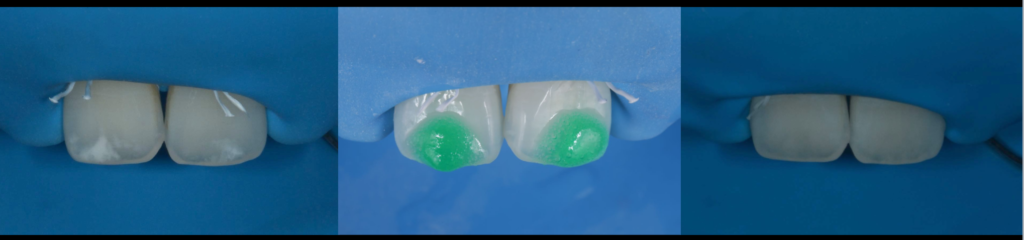

接着ラバーダム

根管治療、虫歯治療、接着修復時において、可能な限り無菌的な環境で行うことが最も重要です。

詳しく見る